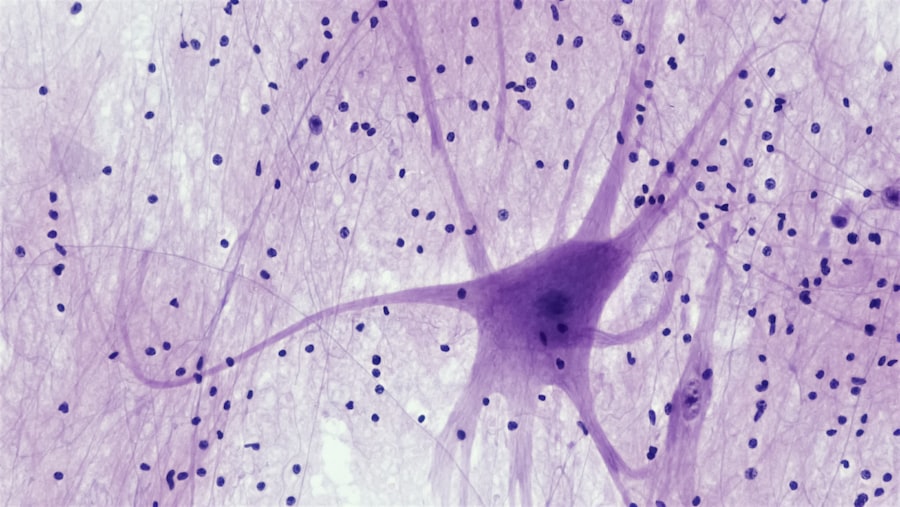

The Science behind Neuro-Adaptation

The science of neuro-adaptation is rooted in the study of neuroplasticity, which has gained significant attention in recent years. Researchers have discovered that the brain can reorganize itself at both the cellular and structural levels in response to various stimuli. This means that when you engage in new activities or face challenges, your brain can physically change its structure to accommodate these experiences.

For instance, learning a new language or instrument can lead to increased gray matter in specific areas of the brain associated with those skills. Moreover, neuro-adaptation is influenced by various factors, including genetics, environment, and personal experiences. Your unique combination of these elements shapes how your brain responds to different situations.